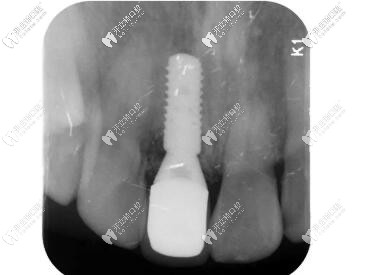

X線顯示:臨時修復體就位良好;

門牙外傷過渡義齒修復

X線片顯示就位良好;

瑞士iti親水BL種植體種植后x片